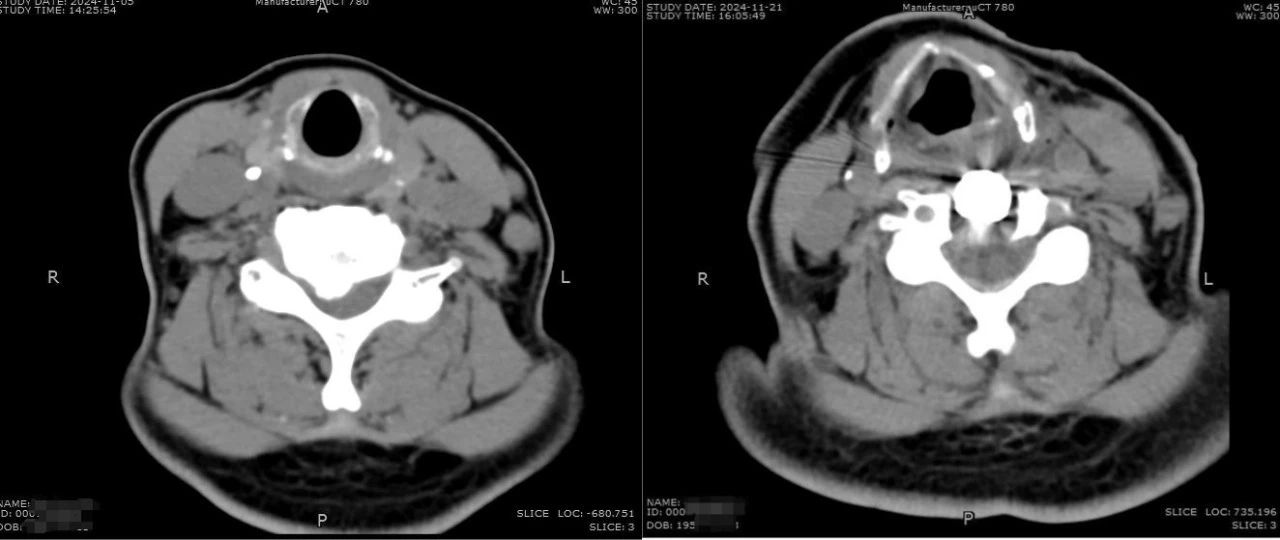

骨伤科副主任医师陈超接诊了张阿姨,了解既往颈肩痛的病史,结合当时剧烈疼痛的表现,当即让张阿姨做了颈椎CT检查。CT影像显示,张阿姨颈椎后纵韧带骨化,增生骨化的后纵韧带、突出的椎间盘共同向椎管内压迫颈脊髓、神经根,这些致压物是造成颈肩部疼痛、头晕、行走不稳的罪魁祸首。根据影像结果和临床表现,陈超初步诊断张阿姨是混合型颈椎病,需要住院治疗。

CT影像对比(左图为术前,右图为术后)

住院期间,张阿姨做了全面检查,结果提示她的颈椎管重度狭窄,人体正常颈椎有7块,张阿姨的C4-C7出现了椎间盘突出、后纵韧带骨化,最严重的是C5,骨化的后纵韧带对椎管的侵占率高达70%。颈椎后纵韧带骨柔软的韧带变成了与骨头硬度一样,硬化的后纵韧带和突出的椎间盘共同压迫了颈脊髓和神经根,这也就是导致张阿姨剧烈疼痛的原因。检查中还发现,张阿姨脊髓压迫的范围广泛且较严重,脊髓已经出现变性。当务之急要尽快手术,解除压迫,缓解症状,同时阻止脊髓由于长期受压进一步的恶化。如果进一步发展,可能不仅仅是疼痛麻木,还可能逐渐的丧失了下肢功能,无法正常走路,甚至出现高位瘫痪。